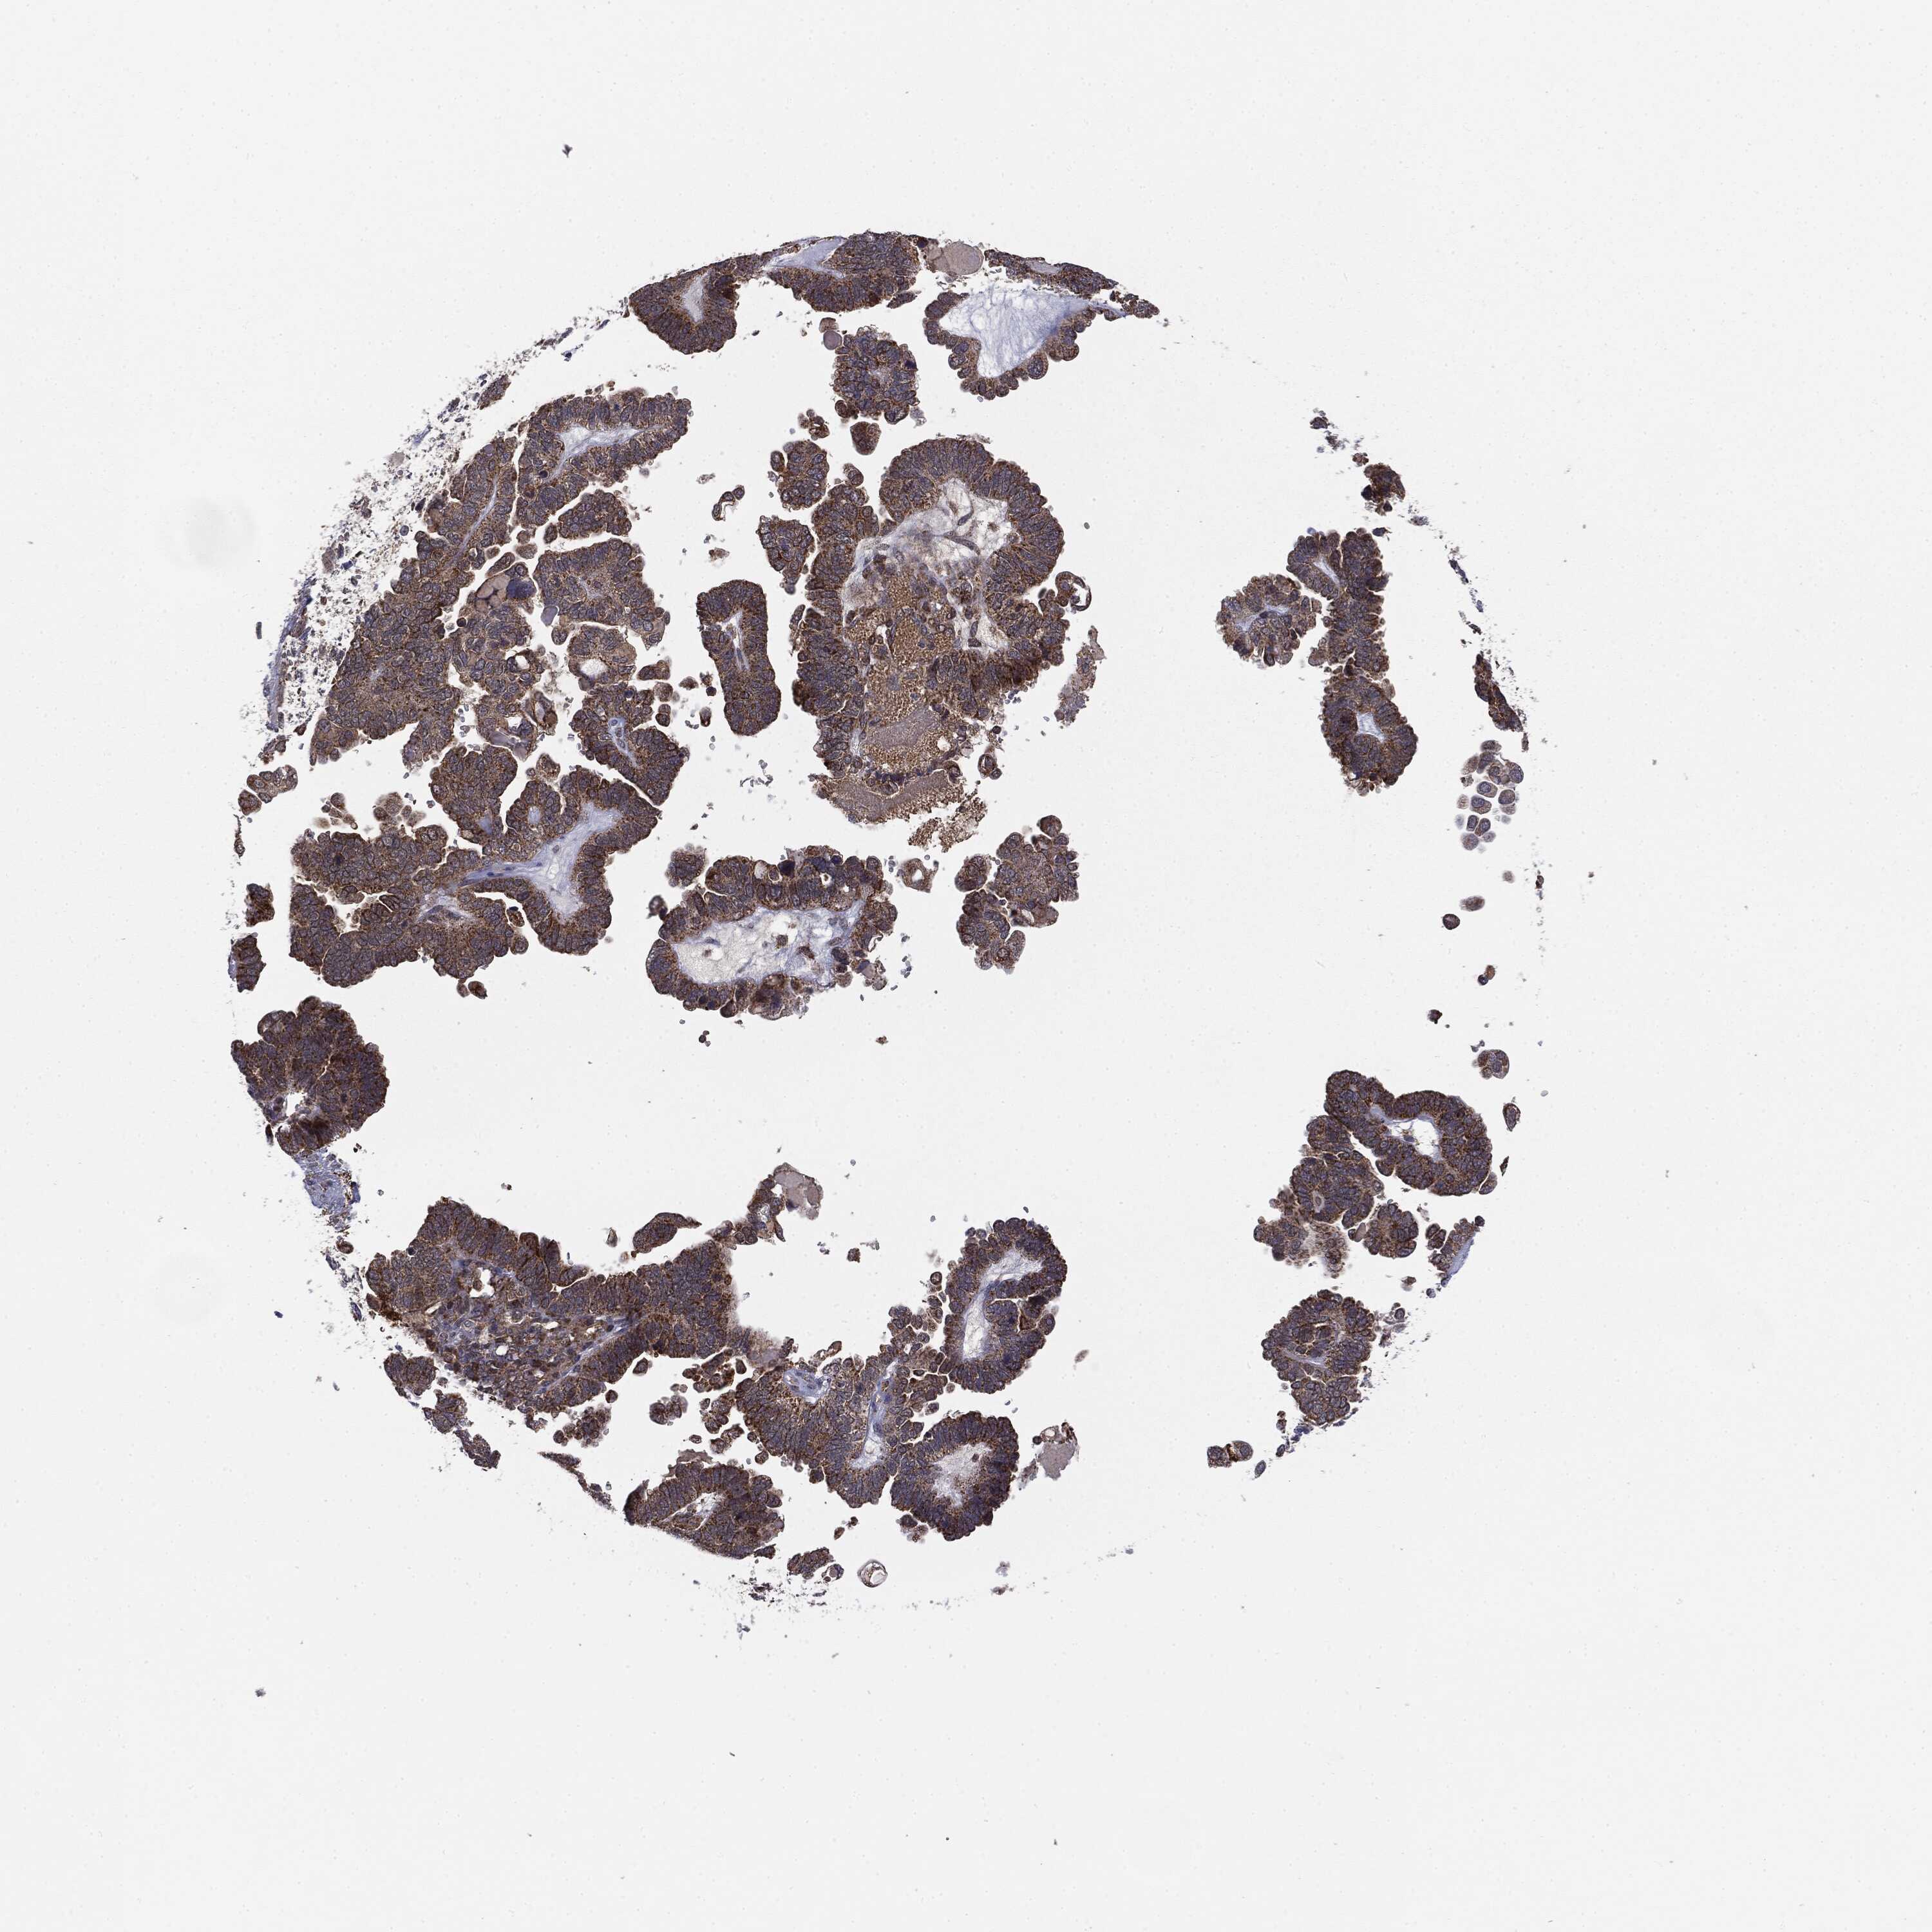

OVARIAN CANCER - Protein expressioni

A mouse-over function shows sample information and annotation data. Click on an image to view it in a full screen mode. Samples can be filtered based on level of antibody staining by selecting one or several of the following categories: high, medium, low and not detected. The assay and annotation is described here.

Note that samples used for immunohistochemistry by the Human Protein Atlas do not correspond to samples in the TCGA dataset.

Antibody stainingi

Antibody staining in the annotated cell types in the current human tissue is reported as not detected, low, medium, or high, based on conventional immunohistochemistry profiling in selected tissues. This score is based on the combination of the staining intensity and fraction of stained cells.

Each image is clickable and will lead to virtual microscopy that enables deeper exploration of all samples and also displays staining intensity scores, fraction scores and subcellular localization as well as patient and tissue information for each sample.

CAB069425

Carcinoma, endometroid